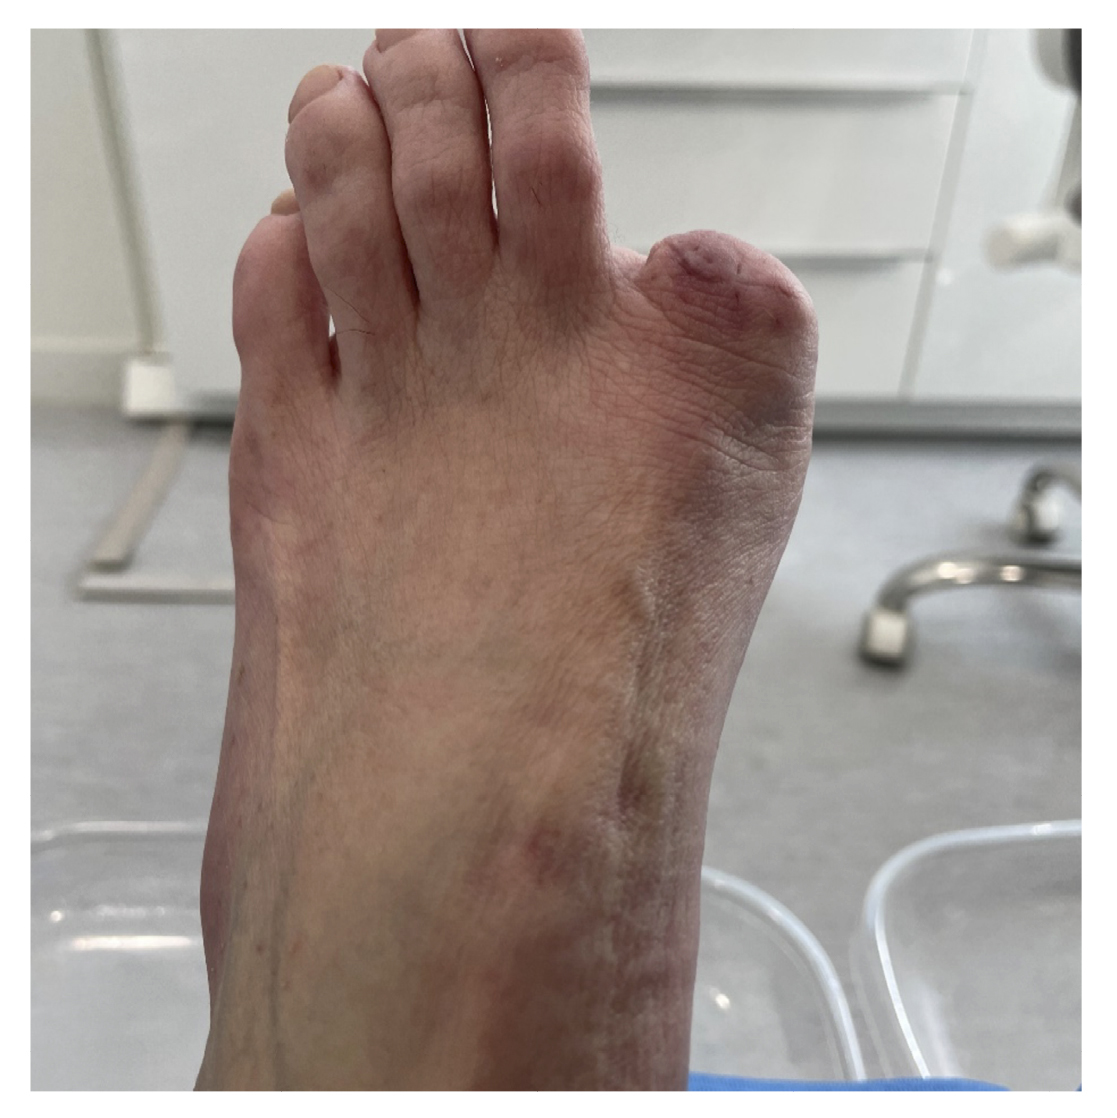

A los 5 días postoperatorios se realizó la primera cura a la paciente, que cursó con buen aspecto y sin infección local. Se explicó el resultado de la anatomía patológica a la paciente y se derivó al servicio de Oncología de su centro hospitalario, y de ahí al servicio de Dermatología y Cirugía plástica donde se realizó la amputación digital (Figura 10). El seguimiento posterior fue llevado por el servicio de Oncología durante los siguientes 6 meses. Después de diferentes pruebas, se determinó que no precisaba otro tratamiento. La Figura 11 muestra la línea de tiempo del caso clínico.

Figura 10. Semana 30. Amputación digital.